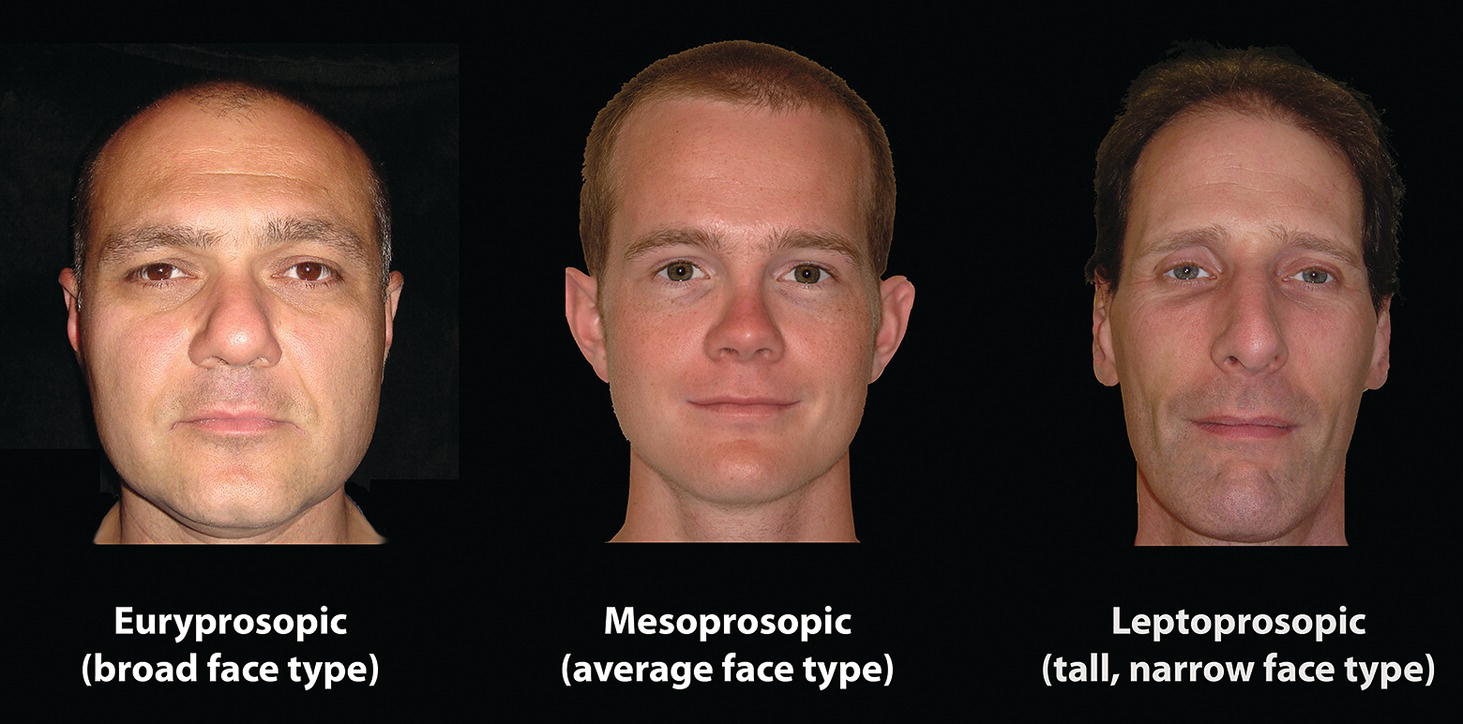

‘It is the common wonder of all men, how among so many millions of faces, there should be none alike’. Sir Thomas Browne (1605–82), English physician and writer, Religio Medici (1643)1 Individual variability is a fundamental principle in human biology. One of the most variable and distinguishable parts of the human body is the craniofacial complex. Clinicians will often compare a patient’s craniofacial measurements and proportions to the so‐called population norms (normative values) or even to classical ideals. However, Simon (1926) stated: ‘all we ever find are variations; an exact, ideal normal does not exist, cannot exist. And this is our enigma; in theory we will never find the normal, in practice we forever feel its need and apply it constantly’.2 The use of population norms may be logically enhanced by evaluating normal ranges of variability. Therefore, clinicians must have a thorough understanding of the normal ranges of variability in every aspect of craniofacial form, depending on age, sex and ethnic variability. Developmental disorders, as well as traumatic injuries and pathological conditions, may lead to deformities of the head and the face. Therefore, clinicians need to have a thorough understanding of the normal anatomy and morphological range of variation of the craniofacial complex in both males and females of different ages and ethnic groups, to act as guidelines when treatment planning the restoration of normal craniofacial proportions. Classifications that are useful for descriptive purposes include: A proportion index provides a numerical expression of the proportionality of a region of the craniofacial complex. The use of proportion indices dates back through the history of craniometry, particularly in the late nineteenth century. Linear (chord) or surface (arc) distances of the skull were measured between a variety of defined craniofacial landmarks; with any two measurements, the smaller was expressed as a percentage of the larger in order to provide a proportion index value. These could be used to provide an indication of skull shape. Figure 8.1 Determination of the normality or abnormality of any craniofacial measurement (or proportion index value) obtained from patients may be evaluated by comparison with the normative values obtained from a normal (average representative) population sample. The normal range of measurements is provided by the mean ±2 standard deviations (SD). The shape of the normal distribution curve shown is determined by the population standard deviation. Craniofacial parameters with small SDs have narrow, taller curves and those with large SDs have broader, flatter curves. Approximately 68% of all values fall within the range of ±1 SD from the mean and 95% within the range of ±2 SD from the mean. The normal range of variability for any craniofacial parameter is taken as being equal to the mean ±2 SDs. Greater differences may be perceived as deformities of gradually increasing severity. The leading researcher in the field of craniofacial anthropometry from the mid‐1960s to the early 2000s was Leslie Farkas, from the University of Toronto. Farkas et al. collected a large quantity of highly relevant anthropometric data between 1968 and 1984, from 2564 individuals.3 These data were used to provide 166 individual facial ratios, presented as proportion indices. In the creation of an index, the smaller measurement is multiplied by 100 (numerator) and divided by the larger measurement (denominator). Thus, a proportion index involves two linear craniofacial anthropometric measurements, with the smaller being expressed as a percentage of the larger. Proportion indices permit objective, quantitative assessment of facial morphology and proportions. Farkas3 identified two basic categories of proportion indices: Each proportion index will have a mean index value and a range of variation for a given population group, based on age, sex and ethnicity. The standard deviation (SD) determines the normal (average) range of variability of an index, from 2 SD below to 2 SD above the mean. Index values within this normal range are regarded as variations of normal proportions.4 Measurements within ±1 SD of the mean are regarded as optimal. The relationship between two measurements is disproportionate if the proportion index value is outside the normal range (Figure 8.1).4 For a number of facial parameters, single morphological measurements or proportion index values may have a large SD and, therefore, wide normal ranges of variation; as such, only measurements or proportion index values which differ considerably from the mean of the population will be perceived as deformities. Conversely, other facial parameters may have very small normal ranges of variability, in which case even a small difference from the mean may be perceived as a deformity. The cephalic index (index cephalicus) is a numerical expression of the ratio between the head width (biparietal diameter) and head length (fronto‐occipital diameter) of a living person. The cephalic index (CI) is calculated by the formula (Figure 8.2): Figure 8.2 Cephalic index. Where: The cephalic index is used in anthropometry to classify head types as (Table 8.1; Figure 8.3): Table 8.1 Classification of anatomical head types Index values according to Martin and Saller.5 Figure 8.3 Head types. The highest cephalic index values occur in the Chinese and the lowest values in African Americans. The larger index values of the Chinese differ significantly from those of whites or blacks (Table 8.2).6 A comparison of the cephalic index values of three ethnic groups was undertaken; North American Caucasians, northern European (German) and eastern European (Czech). The index values indicated a mesocephalic head type for both sexes of North American Caucasians and northern Europeans; and a brachycephalic (short‐wide) head type for the eastern Europeans.6 The head circumference is measured in the horizontal plane around the head, through the glabella and opisthocranion. However, it may be measured across ophyron (the point ‘On’, in the mid‐sagittal plane, of a line tangent to the upper limits of the eyebrows) rather than glabella in order to eliminate the effect of development of the frontal sinuses and superior orbital rims on head circumference.5,7 African Americans have the largest and the Chinese have the smallest head circumference for both sexes. The head circumference is slightly larger for blacks than for whites for both sexes.6 The initial step in facial analysis involves the examination of the face in frontal view in order to assess the overall facial shape. The variety of facial shapes is almost limitless. However, a simple assessment will allow an overall categorization of the basic facial shape. The basic facial shape in frontal view may be any combination of the following: Table 8.2 Cephalic index of three ethnic groups Data modified from Farkas.6 SD = standard deviation. Table 8.3 Head circumference of three ethnic groups Data modified from Farkas.6 SD, standard deviation. Figure 8.4 Facial height‐to‐width ratios. Variations in facial height and width result in an innumerable variety of the three basic facial shapes (round, square and triangular). For example, an oval facial type is a combination of an overall round face combined with increased vertical facial height and/or reduced facial width. The relationship of vertical facial height to facial width is an important indicator of overall facial shape. There are three methods of evaluating the vertical facial height‐to‐width proportion. These may be presented as proportions, percentages or indices: The facial index (index facialis or index of the morphological face height) is a numerical expression of the ratio between the facial height (nasion to menton) and the bizygomatic facial width (zygion to zygion) of a living person. The facial index (FI) is calculated by the formula: Where: The facial index is used in anthropometry to classify faces as (Table 8.4; Figure 8.6): Figure 8.5 Facial types according to Albrecht Dürer. (Modified from Dürer, 15288.) Figure 8.6 Facial types. Table 8.4 Classification of anatomical face types Index values: male according to Garson, 1885;9 and female according to Martin and Saller, 1957.5 The term facial divergence was introduced by the orthodontist‐anthropologist Milo Hellman,10 although the concept had been described by Albrecht Dürer (1528) (Figure 8.7).8 It is essentially a description of the slope or inclination of the face in the sagittal plane (Figure 8.8). It is determined by the sagittal position of soft tissue pogonion (Pog’) and subnasale (Sn) relative to a vertical line dropped from glabella (G’), with the subject’s head in natural head position. The factor that discriminates and distinguishes facial divergence from profile convexity or concavity is the sagittal position of subnasale (Sn) relative to the G’‐Pog’ line. In order for the face to diverge anteriorly or posteriorly, yet not to exhibit signs of convexity or concavity, subnasale (Sn) must be on or nearly on the G’‐Pog’ line; i.e. the upper facial plane (UFP, G′‐Sn) and the lower facial plane (LFP, Sn‐Pog’) are in a straight line, but diverge anteriorly or posteriorly. Figure 8.7 Facial divergence according to Albrecht Dürer. (Modified from Dürer, 15288.) Figure 8.8 Facial divergence. Anthropometric data from North American Caucasian males and females with untreated Class I dental occlusions describing normal facial divergence and ranges of variability has been provided.11 Mean values of facial divergence are negative, with the faces being slightly posteriorly divergent. Anterior divergence does not occur until two standard deviations from the mean. Facial divergence is essentially an ethnic variation in facial profile form. With a straight profile, i.e. no excessive profile convexity or concavity, anterior or posterior facial divergence is compatible with a normal maxillo‐mandibular and dental occlusal relationship. Figure 8.9 Facial profile contour according to Albrecht Dürer. (Modified from Dürer, 15288.) Figure 8.10 Facial profile contours. The contour of the facial profile may be described as convex, straight or concave. This concept was described by Albrecht Dürer (1528) (Figure 8.9).8 With the patient in NHP, the overall contour of the facial profile may be described by the relationship between two lines: the upper facial plane (UFP), connecting glabella (G’) to subnasale (Sn), and the lower facial plane (LFP), connecting subnasale to soft tissue pogonion (Pog’). In a straight profile, these two lines form a nearly straight line. Such a facial profile is termed orthognathic (Greek orthos: correct or straight; gnathos: jaw). An angle between these two lines indicates facial profile convexity (pogonion behind relative to subnasale in the sagittal plane), or facial profile concavity (pogonion ahead relative to subnasale in the sagittal plane). A convex profile indicates a skeletal Class II jaw relationship (and/or sagittal chin deficiency), and a concave profile indicates a skeletal Class III jaw relationship (and/or sagittal chin excess). However, profile convexity or concavity does not of itself indicate whether the maxilla or mandible/chin is at fault (Figure 8.10). Legan and Burstone12 described the angle of facial convexity for the soft tissue profile. It is formed by the two intersecting lines, the UFP (G′‐Sn) and the LFP (Sn‐Pog′). The mean value is estimated to be 12° ± 4°. An increase in the angle in a clockwise direction is positive; anticlockwise is negative. A high positive value suggests facial profile convexity and a Class II skeletal jaw relationship; a smaller positive value, or a negative value, suggests facial profile concavity and a Class III skeletal jaw relationship. However, the value of this angle does not reveal whether the maxilla or mandible/chin is responsible for the sagittal jaw discrepancy. Figure 8.11 Angle of facial profile convexity (facial contour angle). Downs13 described the angle of convexity, formed by the intersection of line nasion to point A (NA) and line point A to pogonion (A‐Pog). Superior extension of the A‐Pog line forms an angle with the NA line; if behind the NA line, the angle is read as positive, indicating a Class II (convex) skeletal profile. A negative angle of convexity indicates a Class III (concave) skeletal profile. Downs provided a range of values from −8.5° to 10°, with a mean of 0°. Again, as with the facial contour angle, the angle of convexity does not determine the localization of the deformity to the maxilla or mandible/chin. An investigation was carried out with the objective of assessing how lower facial profile convexity influences perceived attractiveness. The lower facial profile of an idealized image was altered incrementally between 14° and −16°, creating a range of images which were evaluated by pretreatment orthognathic surgery patients, laypeople and clinicians. A straight profile was perceived as most attractive and greater degrees of convexity or concavity deemed progressively less attractive, but a range of 10° to −12° was deemed acceptable; beyond these values surgical correction was desired. Patients were most critical, and clinicians were more critical than laypeople.14 The facial angle indicates the relative sagittal prominence of soft tissue pogonion. It is formed by the intersection of the true horizontal plane (or Frankfort Horizontal plane) with a facial vertical plane (N′‐Pog’). The angle should be approximately 90°–92°. A greater angle indicates prominence of soft tissue pogonion; an angle less than 90° indicates retrusion of soft tissue pogonion. The soft tissue facial angle does not of itself determine the aetiology of the sagittal position of soft tissue pogonion, which may be due to one or a combination of: Consequently, the facial angle must be used in conjunction with other measurements and analyses. In addition, when constructing the facial vertical line (N’‐Pog’), if the sagittal position of nasion is not acceptable, it may be adjusted to a more ideal position. The alternative is to use soft tissue glabella (G’) rather than nasion. Downs13 described the facial angle as the inferior inside angle in which the facial line (N‐Pog) intersects the Frankfort Horizontal plane. Downs found a mean value of 88° with a range of 82°–95°. It indicates the relative sagittal position of the mandible/chin to the upper face. Figure 8.12 Facial angle. FH, Frankfort Horizontal plane; TrH, true horizontal plane. Figure 8.13 The relationship of the cranial base angle (saddle angle) and anterior cranial base length on the jaw relationship. The relationship of the anterior to the posterior cranial base is of particular importance in the diagnosis of facial profile contour. This relationship depends on the extent of growth at the sphenoethmoidal and spheno‐occipital synchondroses. The cranial base angle (or saddle angle) represents the orientation of the anterior cranial base (SN line) relative to the posterior cranial base (S‐Ba line).15 The average adult values (bearing in mind that there is negligible change in this angle after the age of six years) for the angle N‐S‐Ba are16: As such, the cranial base angle is an important determinant of craniofacial form, as it influences the sagittal position of the face relative to the neurocranium and the sagittal prominence of the mandible relative to the maxilla. A significantly increased cranial base angle contributes to a skeletal Class II jaw relationship, whereas a reduced cranial base angle contributes to a skeletal Class III jaw relationship. If basion is difficult to identify on a lateral cephalometric radiograph, articulare may be used instead, i.e. the posterior cranial base is drawn between sella and articulare. The average adult values for the angle N‐S‐Ar are16: The anterior cranial base length, measured from sella to nasion, may also influence the jaw relationship. For example, increased anterior cranial base length may lead to a Class II jaw relationship, with the maxilla ahead of the mandible in the sagittal plane, whereas reduced cranial base length may lead to a Class III jaw relationship, with the maxilla behind the mandible in the sagittal plane. The average adult values for the anterior cranial base length are16: Figure 8.14 Parasagittal profile contour. An additional and extremely important consideration is the description of the parasagittal profile (Figure 8.14). It is necessary to evaluate the sagittal relationships of the soft tissues from the infraorbital area to the paranasal area to the parasymphyseal area. For example, maxillary hypoplasia may lead to lack of bony support and flattening in the infraorbital region and paranasal hollowing; with a normal parasymphyseal area, this will lead to the appearance of a concave parasagittal profile. The directional pattern of facial growth has a significant effect on facial profile form. Deviations from the normal pattern of jaw growth may be in a predominantly vertical or horizontal direction. Alternative terms are hyperdivergent facial growth pattern (referring to the excessive divergence of the maxillary, occlusal and mandibular planes in relation to each other and to the anterior cranial base).17 Such a pattern of growth leads to a hyperdivergent facial type, alternatively termed a high angle patient (referring to the increased mandibular plane angle), long face deformity or long face syndrome.18 If the hyperdivergent growth is the primary aetiology to an anterior open bite, the terms skeletal open bite or apertognathia (Latin apertus: open; Greek gnathos: jaw) may be used.19,20 The maxilla rotates downward and backward (posterior vertical maxillary excess), as does the mandible during growth. This leads to reduced sagittal projection of the chin. Such a vertical facial growth pattern will tend to be associated with a posterior pattern of mandibular growth rotation. Figure 8.15 Hyperdivergent, ‘high angle’ facial type.

Facial type: profile view (norma lateralis)

Facial divergence